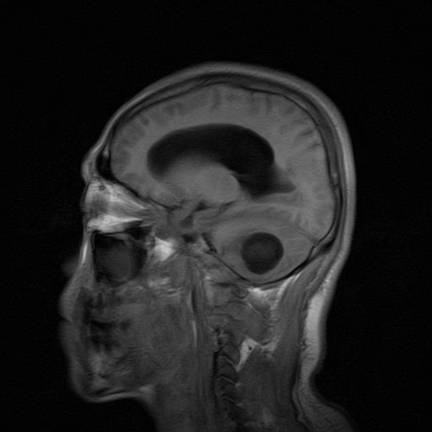

标题: MRI2064:少见病例。男性52,视力下降多年。 [打印本页]

标题: MRI2064:少见病例。男性52,视力下降多年。

四脑室区见混杂信号占位影,脑室系统扩张明显,临近结构显著受压称位,患者52岁,多考虑室管膜瘤可能性大

考虑第四脑室室管膜瘤并梗阻性脑积水;部分性空蝶鞍;左侧上颌窦粘膜下囊肿。

考虑第四脑室室管膜瘤【血供丰富血管母细胞瘤可能】并梗阻性脑积水;部分性空蝶鞍;左侧上颌窦粘膜下囊肿。

比较典型的脉络丛乳头状瘤并脑积水,鉴别小脑蚓部血管母细胞瘤。